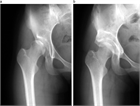

1. 寛骨臼の形成不全により、関節の安定性が障害された状態を寛骨臼(臼蓋)形成不全(acetabular dysplasia)という。

1. 寛骨臼(臼蓋)形成不全は小児から高齢者までに認められ、変形性股関節症のリスク因子である(推奨度1)

1. 股関節単純X線像で寛骨臼(臼蓋)形成不全があり、股関節痛がある場合は、専門医へ紹介する(推奨度1)